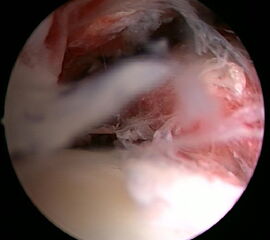

Ein aktuelles systematisches Review zur arthroskopisch-assistierten Frakturversorgung (AORIF) am Sprunggelenk identifizierte bei 495 von 782 Patienten (63,3%) chondrale Verletzungen 54. Weder durch die klinische Untersuchung noch mit konventionellen Röntgenaufnahmen oder mittels CT-Bildgebung lassen sich diese Verletzungen zuverlässig diagnostizieren. Aus diesem Grund rückt die arthroskopisch-assistierte Frakturversorgung am oberen Sprunggelenk zunehmend in den Fokus. Die Arthroskopie ermöglicht im Rahmen der Frakturversorgung sowohl die Kontrolle der Reposition als auch die Beurteilung und Therapie von intraartikulären Pathologien. Während sich die arthroskopisch-unterstützte Versorgung einiger Frakturen bereits etabliert hat (z.B. proximale Tibiafraktur) gehört der Einsatz der Arthroskopie bei der Frakturversorgung des oberen Sprunggelenks in den allermeisten Kliniken noch nicht zum Versorgungsalltag 155 Im Gegenteil, in einer aktuellen amerikanischen Datenbankanalyse des United Healthcare Orthopedic Datasets wurden zwischen 2007 und 2011 insgesamt 32 307 Patienten identifiziert, die mittels ORIF an einer Sprunggelenksfraktur versorgt wurden. In weniger als einem Prozent erfolgte eine arthroskopisch-assistierte Versorgung 55. Dem gegenüber stehen arthroskopische Studien der vergangenen Jahre, die zeigen konnten, wie häufig es zu intraartikulären Verletzungen bei Sprunggelenksfrakturen kommt. Das Risiko für diese intraartikulären Begleitverletzungen nimmt mit der Komplexität der Fraktur zu 5657. Es liegt also nahe, dass bei komplexeren Frakturen die Durchführung einer Arthroskopie im Rahmen der Frakturversorgung einen positiven Effekt auf das Behandlungsergebnis hat. Aus Sicht der Autoren sollte es Ziel für die Zukunft sein, die Frakturtypen zu identifizieren, die von einer arthroskopisch-assistierten Frakturversorgung profitieren. Die diagnostische Arthroskopie mit dem Ziel der gleichzeitigen arthroskopischen Therapie ist in der aktuellen S2-Leitlinie bereits eine Level-1b-Empfehlung. In den Abbildungen 20 – 30 ist schrittweise unser Vorgehen zur arthroskopisch assistierten Versorgung einer Trimalleolarfraktur dargestellt.